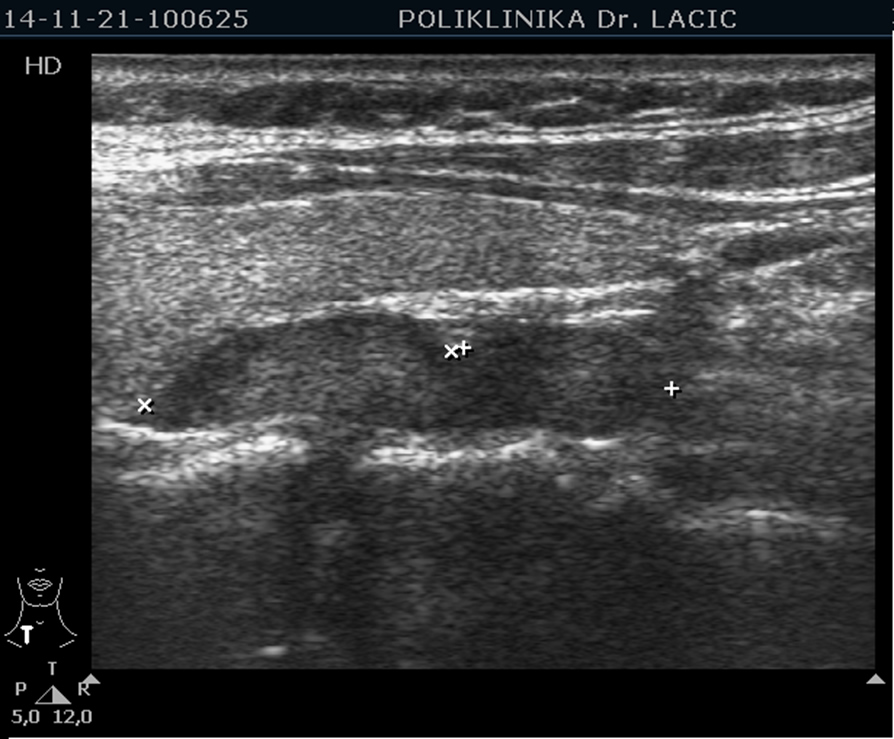

Ultrasound of the thyroid and neck with color Doppler

Ultrasound-guided thyroid puncture with cytological analysis of samples